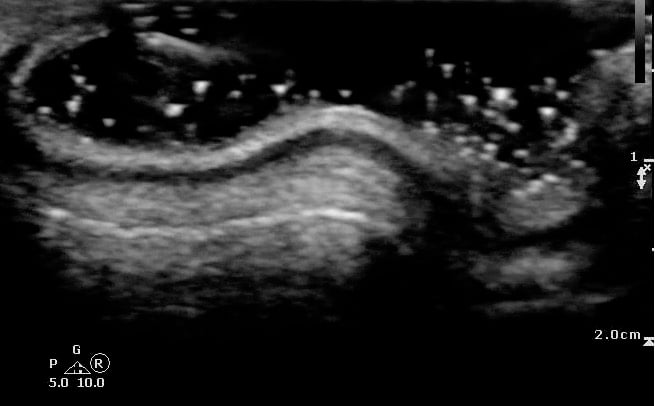

- Figure 1 and 2. Normal Ear

Video 1. Normal Ear - Anterior and posterior skin layers have thin hyperechoic appearance.

- Middle layer containing cartilage appears as a thin hypoechoic band.

- Measurements:

- At the antihelix border the cartilage is thicker; the mean thickness is 0.8 ± 0.1 mm (at the middle third of the antihelix in transverse axis).

- At the lobule the mean thickness is 6.9 ± 1 mm.

- Normal Cartilage: